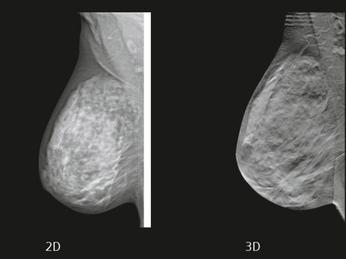

The 3-D breast tomosynthesis is a special type of mammogram that produces a 3-dimensional image of the breast by using several low dose x-rays obtained at different angles, with multiple thin-section images of the breast. 3-D breast tomosynthesis technology has several advantages and disadvantages.